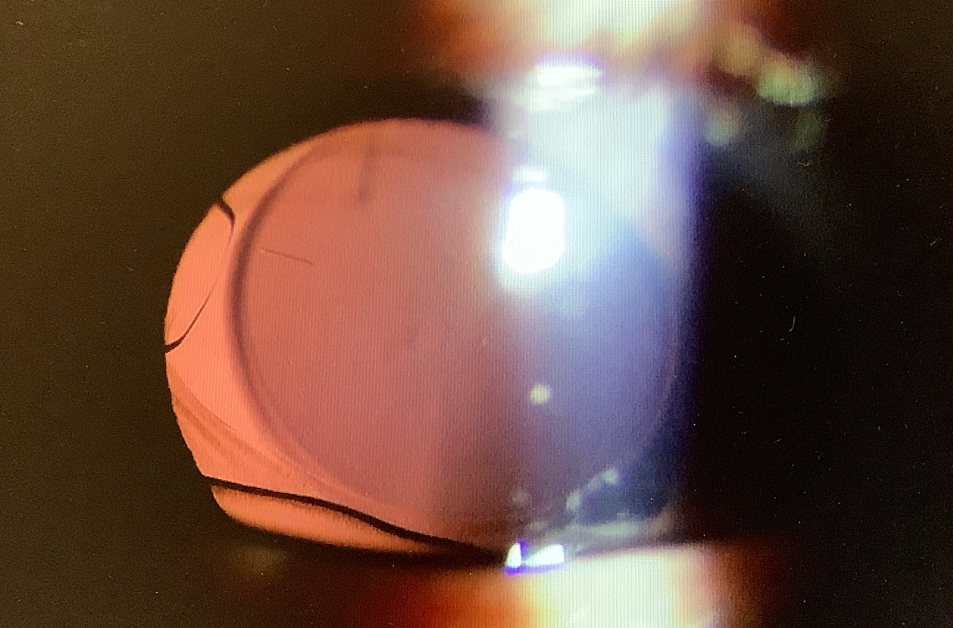

白内障手術後の相談にいらした40代前半の方は、今年の5月にレンティス・コンフォートを使った右眼の白内障の手術を受け、夜の光のグレアが気になるということで、予約をいただいておりました。

今回の患者さんも、『最初はすごく気になっていたのですが、今はだいぶ慣れてきたというか落ち着いてきてしまっています』ということで、結局、何もせずに経過を見るのがよいでしょうということになりました。